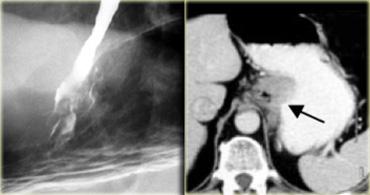

Bên trái là một trường hợp giả co thắt tâm vị khác.

Hẹp đoạn xa mô phỏng co thắt tâm vị, nhưng vị trí hẹp lệch tâm, các bờ vai không đối xứng (mũi tên), và niêm mạc không đều tại đỉnh vùng hẹp.

CT cho thấy thành đáy vị dày lên (mũi tên) do ung thư biểu mô tuyến.